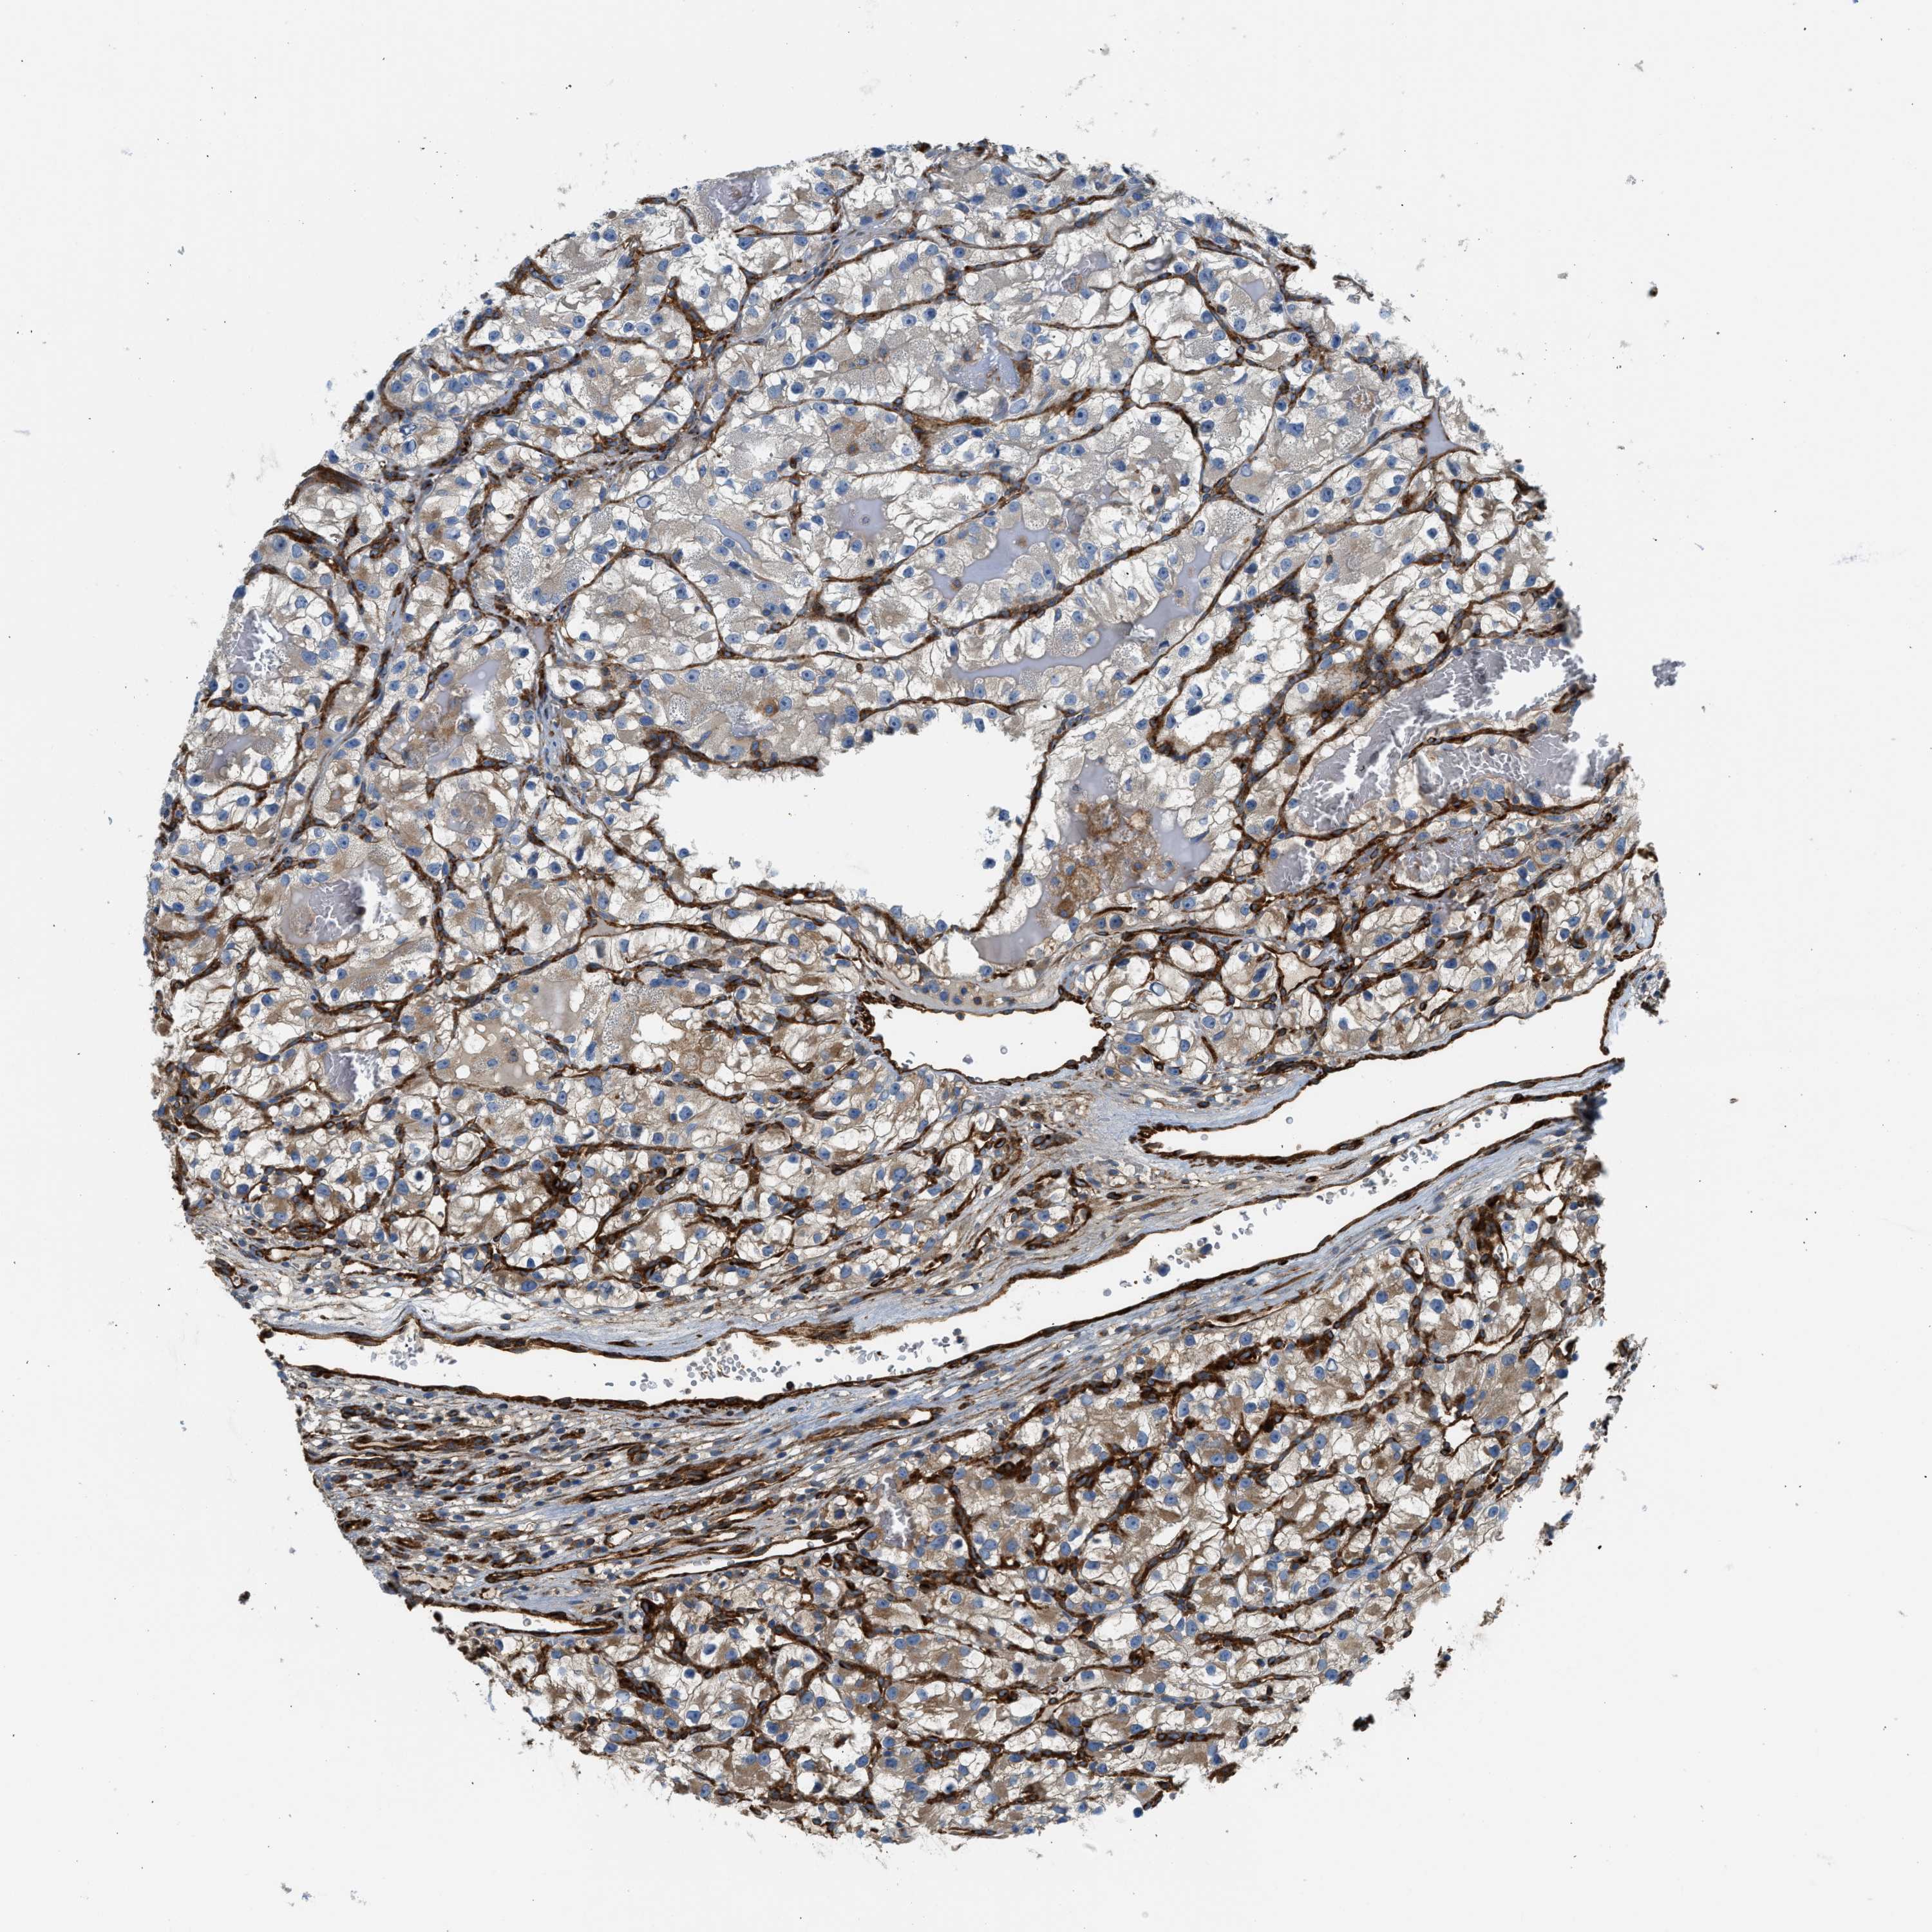

KIDNEY RENAL CLEAR CELL CARCINOMA (TCGA) - Interactive survival scatter ploti

The Survival Scatter plot shows the clinical status (i.e. dead or alive) for all individuals in the patient cohort, based on the same data that underlies the corresponding Kaplan-Meier plots. Patients that are alive at last time for follow-up are shown in blue and patients who have died during the study are shown in red.

The x-axis shows the expression levels (FPKM) of the investigated gene in the tumor tissue at the time of diagnosis. The y-axis shows the follow-up time after diagnosis (years). Both axes are complimented with kernel density curves demonstrating the data density over the axes. The top density plot shows the expression levels (FPKM) distribution among dead (red) and alive patients (blue). The right density plot shows the data density of the survived years of dead patients with high and low expression levels respectively, stratified using the cutoff indicated by the vertical dashed line through the Survival Scatter plot. This cutoff is automatically defined based on the FPKM cutoff that minimizes the p-score. The cutoff can be changed by dragging the vertical line or by entering a cutoff value in the square labeled "Current cut-off".

Under the Survival Scatter plot the p-score landscape (black curve; left axis) is shown together with dead median separation (red curve; right axis). Dead median separation is the difference in median mRNA expression between patients who have died with high and low expression, respectively. It is calculated as follows: median FPKM expression of dead patients with high expression - median FPKM expression of dead patients with low expression. This is intended to aid the user in visually exploring custom cutoffs and the associated p-scores and dead median separation.

Individual patient data is displayed and can be filtered by clicking on one or more of the category buttons on the top of the page. Categories describing expression level and patient information include: high, low, alive, dead, female, male and tumor stages. The scale of the x-axis can be toggled between linear and log-scale by clicking on the "x log" button. Mouse-over function shows TCGA ID, patient information and mRNA expression (FPKM) for each patient.

& Survival analysisi

Kaplan-Meier plots summarize results from analysis of correlation between mRNA expression level and patient survival. Patients were divided based on level of expression into one of the two groups "low" (under cut off) or "high" (over cut off). X-axis shows time for survival (years) and y-axis shows the probability of survival, where 1.0 corresponds to 100 percent.

HIP1 is validated prognostic, high expression is favorable in Kidney Renal Clear Cell Carcinoma (TCGA)

Best expression cut offi

Based on the FPKM value of each gene, patients were classified into two groups and association between prognosis (survival) and gene expression (FPKM) was examined. The best expression cut-off refers the FPKM value that yields maximal difference with regard to survival between the two groups at the lowest log-rank P-value. Best expression cut-off was selected based on survival analysis .

When clicking on this number, the vertical dashed line indicating cut-off, the interactive survival plot, and the Kaplan-Meier curve will be adjusted to show results based on the best expression cut-off.

: 19.66

TCGA RNA samplesi

RNA-seq data is reported as average FPKM (number Fragments Per Kilobase of exon per Million reads), generated by the The Cancer Genome Atlas (TCGA) .

Normal distribution across the dataset is visualized with box plots, shown as median and 25th and 75th percentiles. Points are displayed as outliers if they are above or below 1.5 times the interquartile range. FPKM values of the individual samples are presented next to the box plot.

Average pTPM 17.3

Number of samples 521